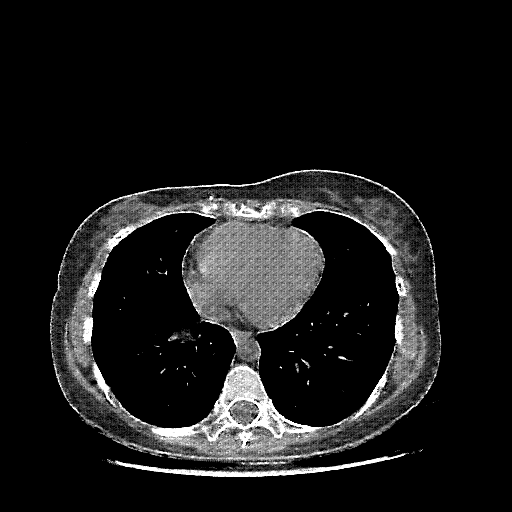

Image Grid

4Γ—3 grid: Rows show different image types (Original NATIVE, Reconstructed NATIVE, Original VENOUS, Generated VENOUS), Columns show windowing techniques (No Window, Lung Window, Mediastinum Window)

Original NATIVE CT scan (input)

Full window (WL 1023.5, WW 4095 β†’ Low βˆ’1024, High +3071)

Generated VENOUS CT scan (A→B translation)